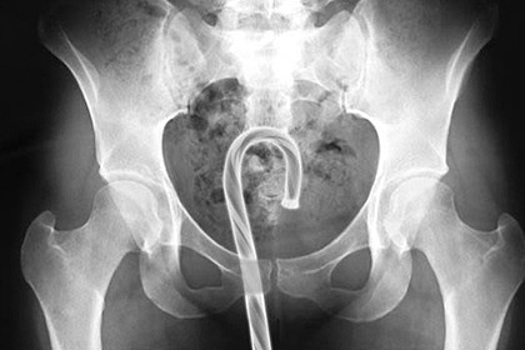

Комиссия США по безопасности потребительских товаров опубликовала список вещей, застрявших в американцах за год. Об этом сообщило издание Adequate Man. Журналисты упорядочили происшествия по отверстиям, куда попадали посторонние предметы. Согласно списку, в уши американцев среди прочего попадали: хлеб, батарейки, солома от веника, стружка от сточенного карандаша. Иногда врачи оставляли небольшие ремарки о случившемся вроде: «Бежал в палочкой в ухе, но упал им на стену» или «свернул бумажные полотенца и засунул в уши, потому что сосед очень громко храпел». В 2017 докторам пришлось вытащить из ноздрей пациентов следующие вещи: розовый воздушный шарик, соску для бутылочки, два магнита, каждый из которых был в своей ноздре. Из горла медики извлекали открытую английскую булавку, пасхальное яйцо, термометр для аквариума. Один из пациентов проглотил ручку, потому что «никто не обращал на него внимание», а другая — несколько скрепок, так как «ей так сказали инопланетяне». Нетипичные предметы врачи вытаскивали и из более деликатных мест. Например, из уретры за 2017 год врачи извлекли пластиковую ложку, кость домино, десятисантиметровую секс-игрушку и коаксиальный кабель. Из влагалища доктора доставали катафот для велосипеда, игрушечную волшебную палочку, наушники и глину. Из одной пациентки пришлось извлекать деньги и телефон, так как ее молодой человек поместил их туда во время секса. Наконец, из анального отверстия врачам пришлось извлечь мяч для гольфа, упаковку жевательного табака, игрушечную ракету и набалдашник для карниза. Пациенты объясняли происшествия разными причинами: лечением запора, облегчением симптомов геморроя, случайным падением в ванной, пьяными экспериментами с друзьями. Один американец и вовсе боролся с тревожностью, засунув бутылку с водой в анальное отверстие.